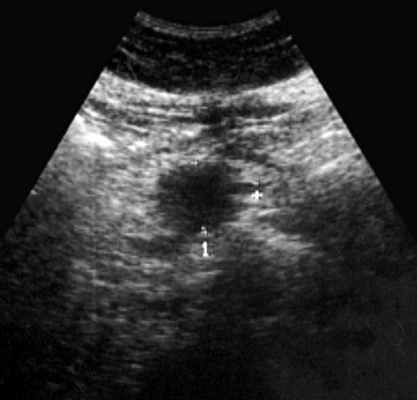

При УЗИ органов брюшной полости: печень в размере не увеличена (4,3-13,3 см), контур ее ровный, паренхима с умеренно выраженными явлениями жировой инфильтрации. Очаговой патологии не выявлено. Внутрипеченочные желчные протоки и вены, портальная (0,9 см) и селезеночная (0,4 см) вены не расширены. Холедох визуализируется фрагментарно, диаметр не превышает 0,8 см. Желчный пузырь не визуализируется (оперативно удален). Поджелудочная железа нормальных размеров (2,9-1,6-2,1 см), контур ровный, равномерно диффузно уплотнена. Вирсунгов проток не расширен. Диаметр сечения пищеварительного тракта на уровне пищеводного отверстия диафрагмы 1,6 см. В желудке натощак много слизи, стенка его не утолщена (0,3-0,5 см). На уровне наружного контура головки поджелудочной железы визуализируется округлой формы с ровными контурами пониженной эхогенности образование с нежной внутренней структурой размером 2,1x3,2 см (рис. 1). При полипозиционном исследовании выявить связь данного образования с головкой железы не удалось. В то же время, локально, на уровне данного образования толщина стенки дистального отдела луковицы двенадцатиперстной кишки составила 0,5 см (в остальных отделах 0,2-0,3 см). Селезенка не увеличена, структура ее однородная. Свободная жидкость в брюшной полости не определяется. Брюшной отдел аорты нормального диаметра (1,8 см). Парааортальные лимфатические узлы не визуализируются. Заключение: состояние после холецистэктомии. УЗ-признаки стеатоза печени, грыжи пищеводного отверстия диафрагмы. Киста головки поджелудочной железы? Для исключения патологии желудка и двенадцатиперстной кишки показано проведение рентгенологического и эндоскопического исследований.

![Эхограмма дивертикула двенадцатиперстной кишки, симулировавшего кисту поджелудочной железы]()

Рис. 1. Эхограмма дивертикула двенадцатиперстной кишки, симулировавшего кисту поджелудочной железы.

Рассматриваемый случай интересен тем, что большой дивертикул двенадцатиперстной кишки при ультразвуковом исследовании симулировал кисту поджелудочной железы. Кисты (псевдокисты) поджелудочной железы встречаются значительно чаще дивертикулов, поэтому вполне естественно заключение о наличии у больной кисты. Однако отсутствие указаний в анамнезе на острый или хронический панкреатит, неудачная попытка проследить связь выявленного жидкостного образования с головкой поджелудочной железы при полипозиционном исследовании, локальное утолщение дуоденальной стенки позволили высказать предположение о возможной прочей патологии и назначить дообследование.